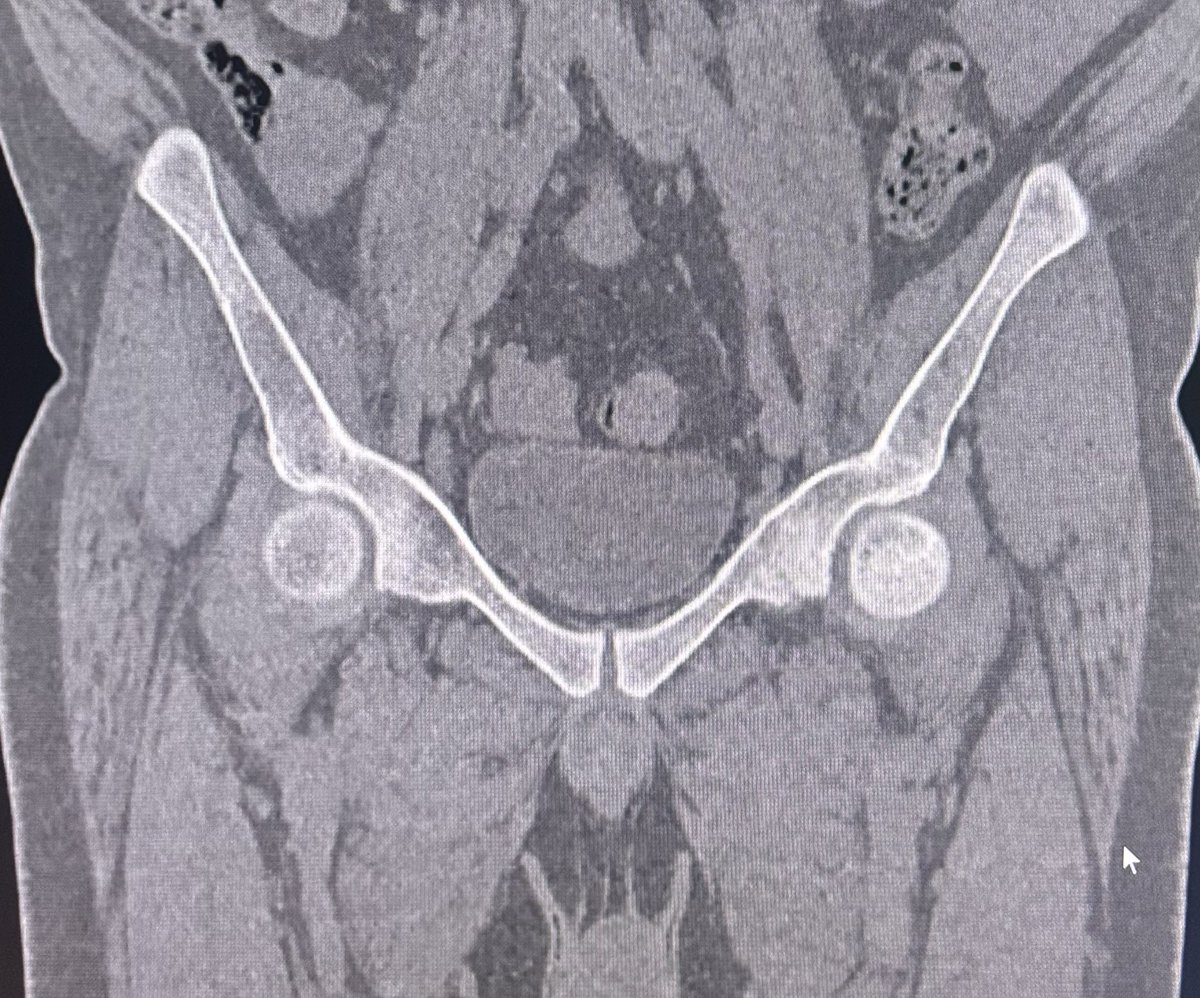

Is every edema along the SI joint Sacroiliitis?

This is a case of 45y/M came for follow up of Sacroiliitis which was reported elsewhere on an MRI 6 months back. What do we see here in addition to marrow edema?

Follow 🧵 for more.

#OrthoRad

#MSKimaging